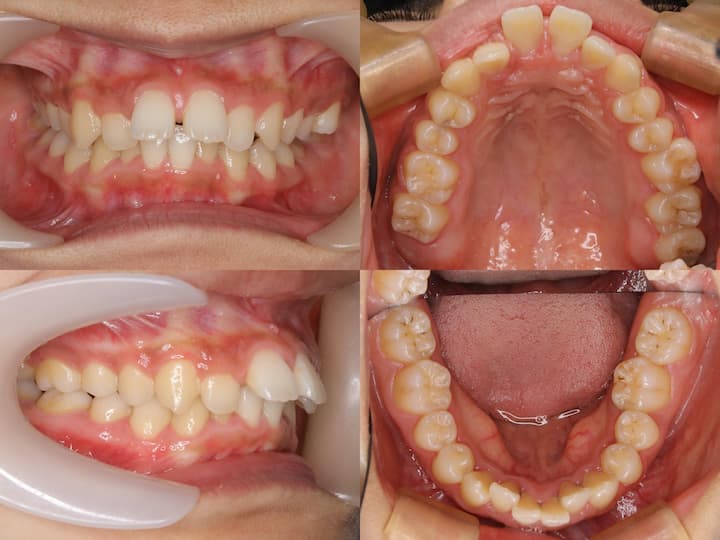

診断所見

初診時の口腔内所見および頭部X線規格写真分析より、以下の所見が認められました。・上下顎前歯部の叢生

・口唇部の突出感

・AngleⅠ級臼歯関係(良好な臼歯関係)

・下顎骨の後方位(ハイアングル症例)

・下顎下縁平面角の増大